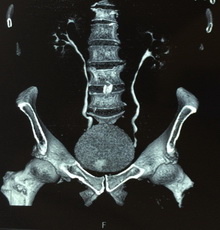

Из анамнеза: с 2013 года периодически отмечает примесь крови в моче с бесформенными сгустками. По месту жительства, при УЗИ выявлено образование мочевого пузыря в области правого устья размером 30*9мм. Выполнена компьютерная томография органов брюшной полости и малого таза, по данным которой образование подтвердилось. Пациент был направлен в клинику урологии Первого МГМУ им. И.М. Сеченова. Госпитализирован для дообследования и определения дальнейшей тактики лечения.

Рис. №2. Мультиспиральная компьютерная томография органов мочевой системы с контрастированием.